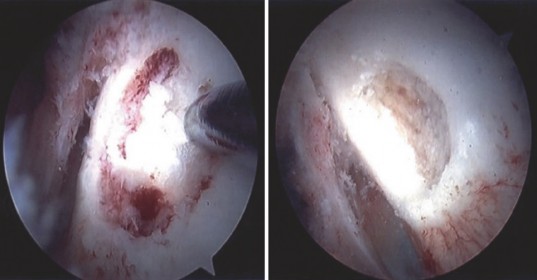

Once access to the central compartment is achieved, a systematic diagnostic arthroscopy is performed. The surgeon evaluates the acetabular labrum, the ligamentum teres, and the chondral surfaces of the acetabulum and femoral head. In cases of intra-articular osteoid osteoma, the central compartment often exhibits profound, hyperemic synovitis.

The surgeon will immediately encounter the reactive synovitis, which can be thick, villous, and highly vascular. A thorough synovectomy is performed using an arthroscopic shaver and radiofrequency wand. This step is critical not only for alleviating the patient's inflammatory symptoms but also for exposing the underlying bony architecture of the femoral neck. Meticulous care must be taken during the synovectomy along the posterosuperior and posteroinferior aspects of the neck to avoid injuring the ascending retinacular vessels.

Locating the nidus is the most challenging aspect of the procedure. The overlying cortex may appear entirely normal, or it may exhibit subtle neovascularization, a localized hyperemic blush, or a slight cortical prominence.

Once the location is confirmed, a high-speed arthroscopic burr is used to carefully unroof the overlying cortex. As the cortex is breached, the nidus typically appears as a distinct, hyperemic, cherry-red, granular tissue mass that contrasts sharply with the surrounding white, sclerotic bone.

Curettes and pituitary rongeurs are utilized to meticulously excavate the nidus. It is imperative to obtain adequate tissue samples for histopathological analysis to definitively confirm the diagnosis of osteoid osteoma and rule out malignancy or infection. Following the removal of the gross nidus, the high-speed burr is reintroduced to extend the resection margin by 1 to 2 millimeters into the surrounding reactive bone, ensuring complete eradication of the tumor and minimizing the risk of recurrence.